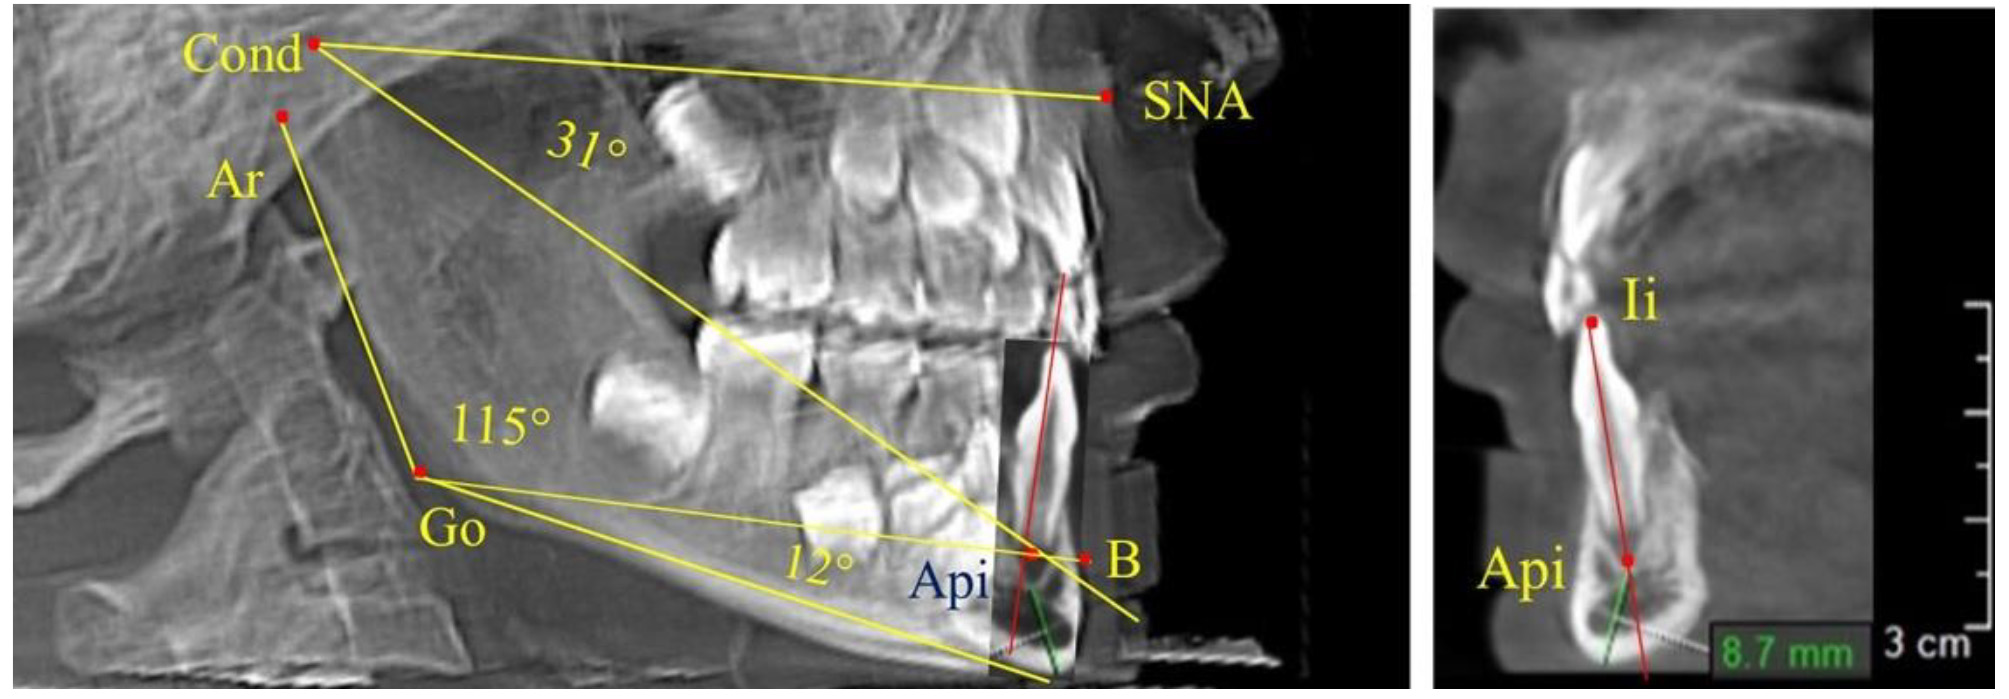

Таким образом, в периоде молочного прикуса с оптимальными окклюзионными соотношениями, несмотря на линейные размеры в вертикальном и сагиттальном направлении, которые, безусловно, меньше параметров взрослых людей, величина основного угла гнатической части лица SNA-Cond-Api соответствовала параметрам людей с полностью сформированным физиологическим прикусом постоянных зубов. Анализируя данные рентгенограмм детей в периоде сменного прикуса, отмечено, что величина основного угла гнатической части лица SNA-Cond-Api, так же как в молочном и постоянном прикусе, в норме составляла от 28 до 32°. В то же время угол нижней челюсти и его составляющие отличались вариабельностью параметров при различных показателях нижнечелюстного угла. Достоверных различий угла гнатической части после смены нижних медиальных резцов и прорезывания первых постоянных моляров (4 ребенка) не было; происходил очередной этап подъема высоты прикуса и увеличение линейных размеров костей гнатической части, однако угловые параметры были относительно стабильны. После смены всех резцов и замены первых молочных моляров первыми премолярами (6 человек) увеличивались линейные размеры при сохранившихся угловых показателях гнатической части лица (рис. 5).

Рис. 5. Варианты ТРГ после прорезывания ППМ и нижних резцов (а), всех резцов и первых премоляров (б)

Таким образом, в период сменного прикуса с оптимальными окклюзионными соотношениями, несмотря на увеличение линейных размеров в вертикальном и сагиттальном направлении, по сравнению с прикусом молочных зубов, величина основного угла гнатической части лица SNA-Cond-Api соответствовала показателям как постоянного, так и молочного прикуса с физиологическими окклюзионными соотношениями.